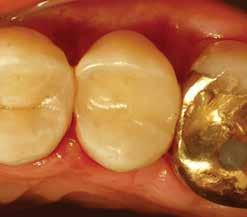

MarchApril 2026 ISSUU by Florida Dental Association - Issuu